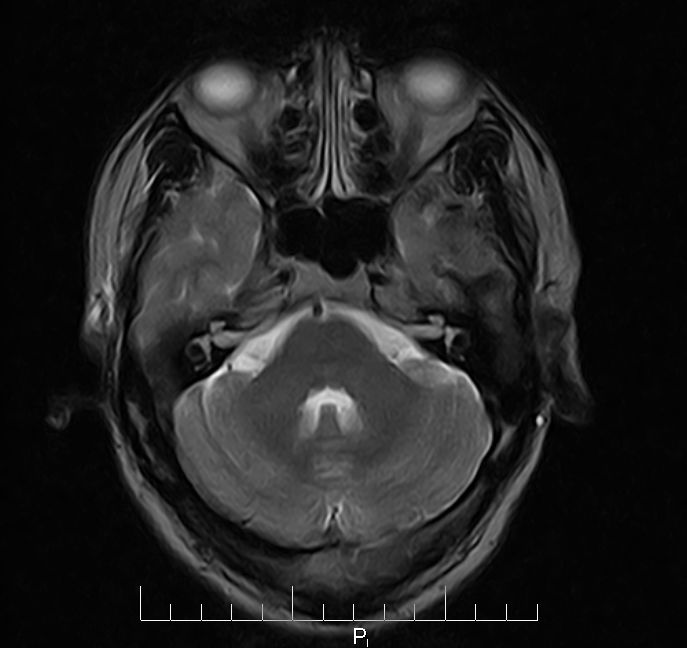

标题: MRI2379:30岁,男,癫痫10年,请各位看一下;CT示:左颞叶钙 [打印本页]

标题: MRI2379:30岁,男,癫痫10年,请各位看一下;CT示:左颞叶钙

左颞叶区见不规则点状混杂信号影

支持2楼 左颞叶区见不规则点状混杂信号影,考虑动静脉畸形。

考虑左侧颞叶脑血管畸形(avm)。----t1低等高混杂信号,t2等高信号周边较多流空血管影[冠状位明显],mra左侧大脑中动脉受压,远侧聚集.

考虑avm,建议行增强扫描,看供血a与引流v,以明确诊断。